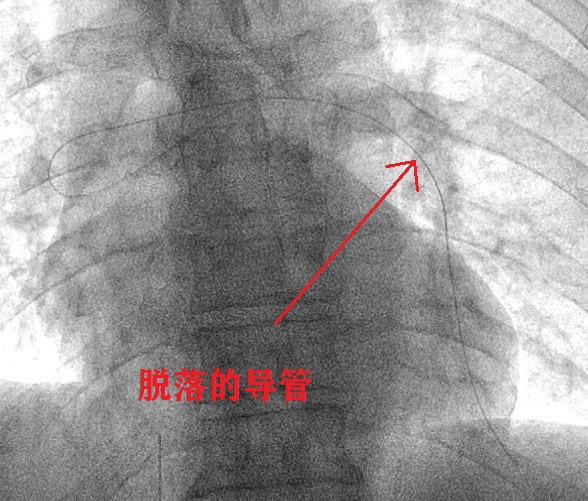

介入医学科第一时间组织科室人员会诊,经过详细的术前讨论及准备,征得患者同意后,确定了经股静脉穿刺介入“抓捕”该导管的手术方案。

由于该导管两头均在血管分支远端,无法单纯利用圈套器进行套取。针对这一手术难点,介入医生选择在X线透视下,利用造影导管对异物进行反复钩挂。经过1个多小时的努力,终于将异物一端从上肺静脉内挑拨到了肺动脉主干内,并利用圈套器成功取出了全部脱落的长约50cm的PICC导管,取出后造影未发现明显血管损伤,目前患者状态稳定。